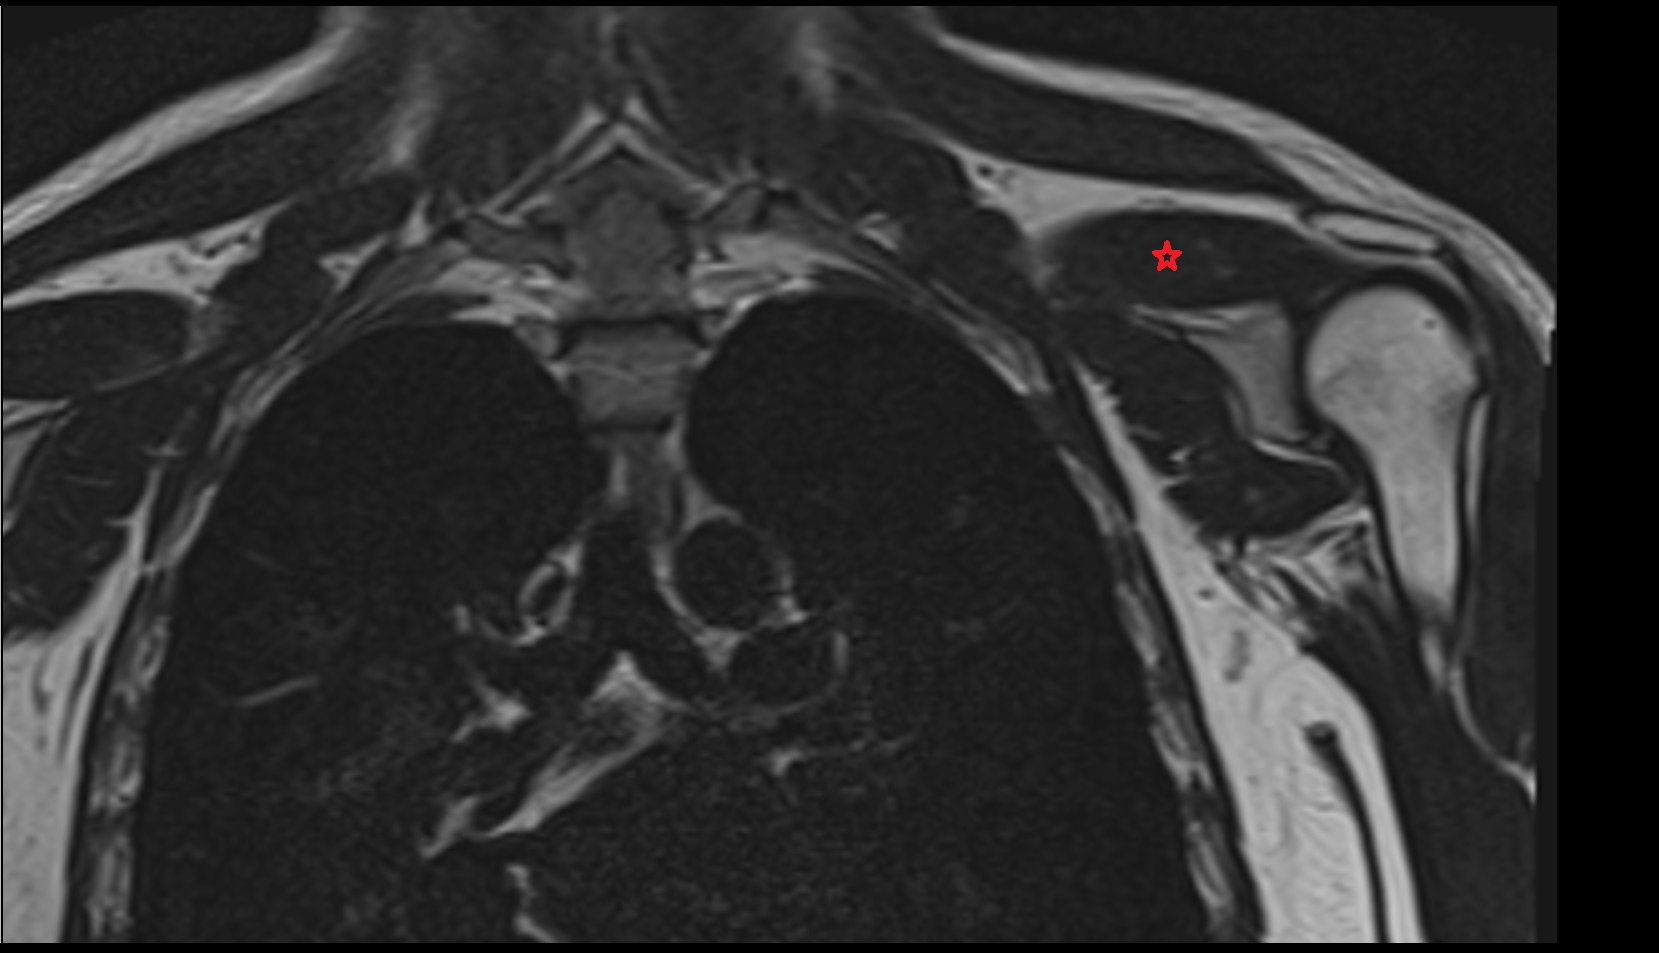

- Adipose tissue (Shoulder)

- Subacromial space